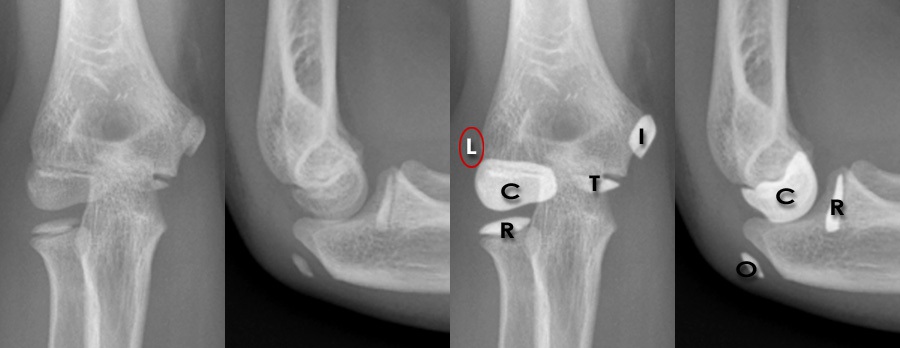

X Ray Elbow

Elbow x-ray - labelling questions | Radiology Case | Radiopaedia.org Anatomy of Elbow X-rays - YouTube Elbow series | Radiology Reference Article | Radiopaedia.org EMRad: Radiologic Approach to the Pediatric Traumatic Elbow X-ray | X Ray Elbow